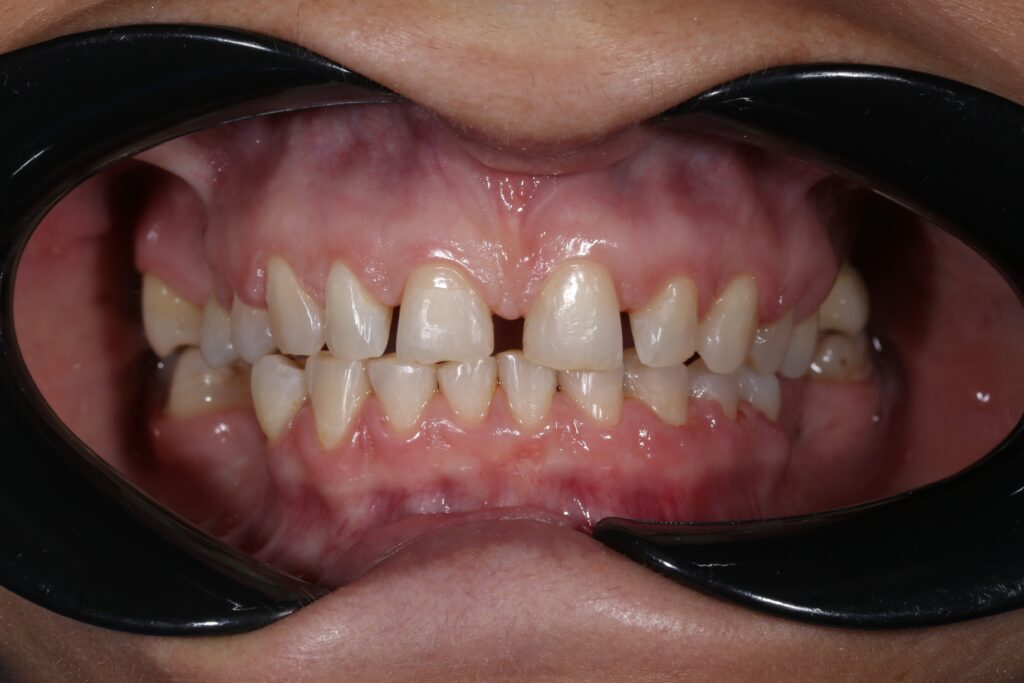

Ситуация до лечения

Пациентка 39 лет была направлена стоматологом-ортопедом для ортодонтической подготовки перед протезированием.

Из-за множественных давних удалений жевательных зубов, произошла деформация зубных рядов, зубы разъехались в область удаленных, что затрудняло протезирование в момент обращения к ортопеду.

Так же можно отметить сильное снижение высоты прикуса (верхние зубы на 100% перекрывали нижние, что вызывало хроническую травму десны), а также повышенную стираемость твердых тканей зубов,

что является следствием повышенной нагрузки, которую много лет испытывали передние зубы, в связи с отсутствием жевательных зубов.

пациент до брекетов